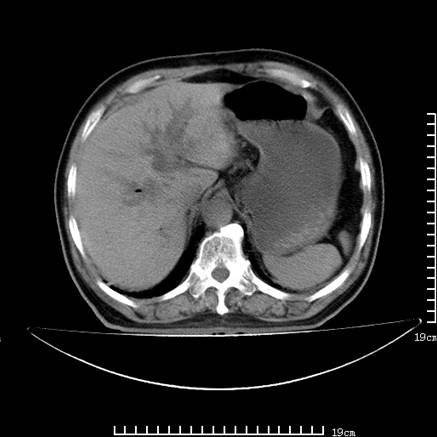

以下是引用lirenxiong在2008-7-19 22:01:00的发言:[br]胆总管结石并胆系感染,胆囊切除术后改变!左肾未见!左肾上腺增生肥大?请全腹扫描,增强!

以下是引用lirenxiong在2008-7-19 22:01:00的发言:[br]胆总管结石并胆系感染,胆囊切除术后改变!左肾未见!左肾上腺增生肥大?增强!